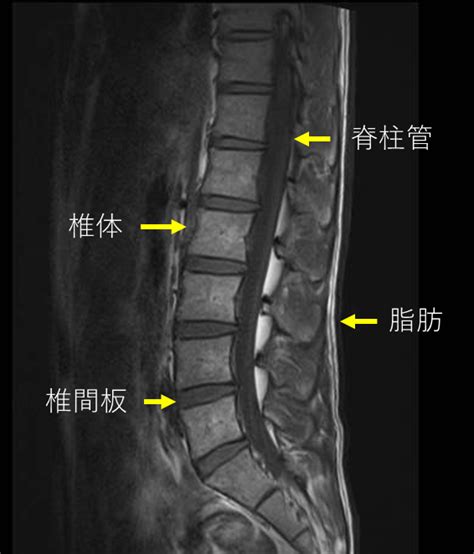

追加検査(MRI/CT)の必要性と判断の目安(痛みが取れない場合)

といった場合に、MRIやCTなどの検査が検討されることがあると言われています。

MRIは筋肉や靭帯などの状態を、CTは骨の細かい形状を確認しやすい検査方法とされています。ただし、必ずしも全員に必要というわけではなく、症状や経過を見ながら判断されることが多いようです。